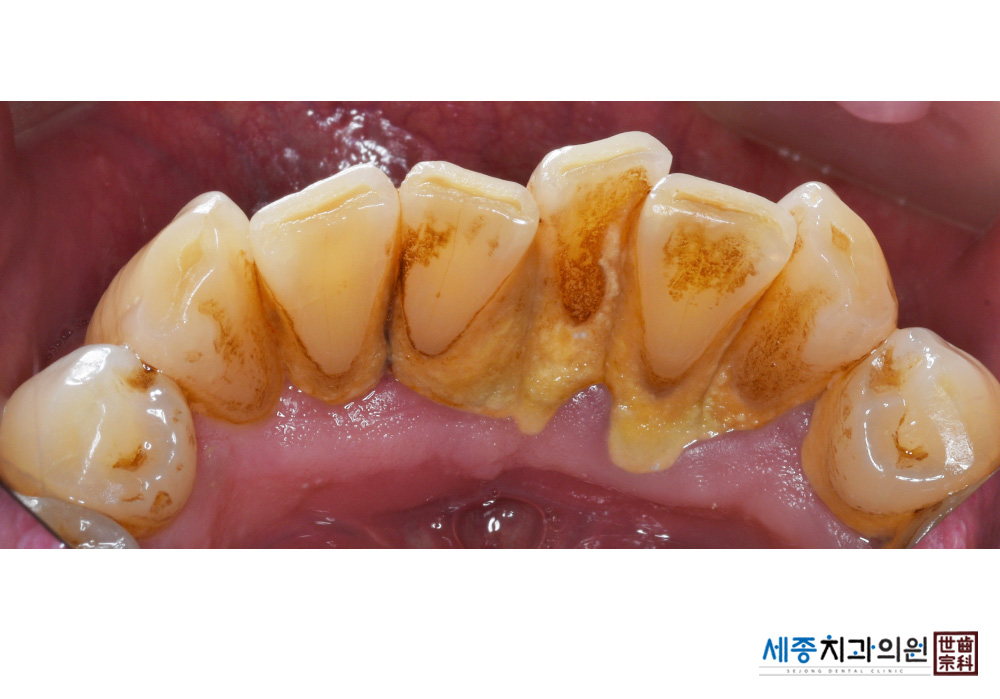

[스케일링] 치주질환 예방 스케일링

치료전 : 2020-01-28

치료후 : 2020-01-28

가글마취&저주파 스켈러를 사용한 스케일링